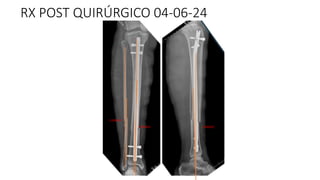

RX POST QUIRÚRGICO 04-06-24

INTRA QUIRURGICO (04/06/24)

-ENCLAVADO ENDOMEDULAR CON CLAVO UTN PARA TIBIA DERECHA